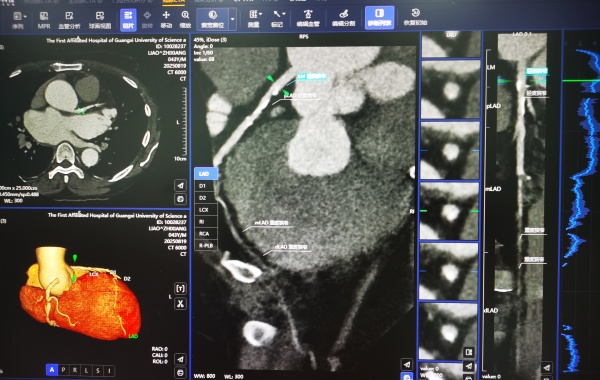

放射诊断也随着AI人工智能的发展进入到AI时代,AI算法能够帮助快速识别影像中的异常,如肿瘤、骨折等,作为医生的智能助手,对可疑病灶进行粗筛选,节省医生的时间,帮助医生提高诊断水平。

一些AI技术系统还结合大量的既往病史来评估、预测疾病风险提供给医生作为诊疗参考,如AI在肺部发现可疑结节后快速标注,由医生进一步分析判断,提高了对肺癌的早期检出率。